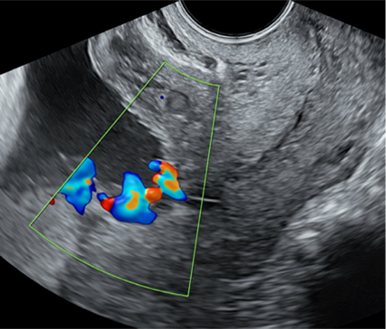

전치혈관은 막에 싸여 있지 않은 제대동맥 혹은 정맥이 자궁경부내구 주위(< 20 mm)에 위치하는 것으로 정의하며 산전에 진단되면 주산기 생존율이 100%이지만 산전진단되지 않은 경우 주산기 사망률이 56%에 이를 정도로 산전진단이 중요합니다(그림2). 진단은 질초음파로 자궁경부내구 근처에 혈관이 있는지 컬러도플러를 확인하여 민감도 100%로 쉽게 확인할 수 있으므로 위험인자가 있는 임신부에서 검사를 시행하는 것이 권장됩니다. 전치혈관의 위험인자는 전치태반, second trimester low-lying placenta, bilobed placenta, succenturiate placenta, 다태임신 등입니다. 임신 중기에 전치혈관이 확인되었더라도 자연소실되는 경우도 있으므로 제3삼분기에 전치혈관에 대한 재평가가 권장됩니다.

그림 2. 전치혈관. from ISUOG practice guidelines